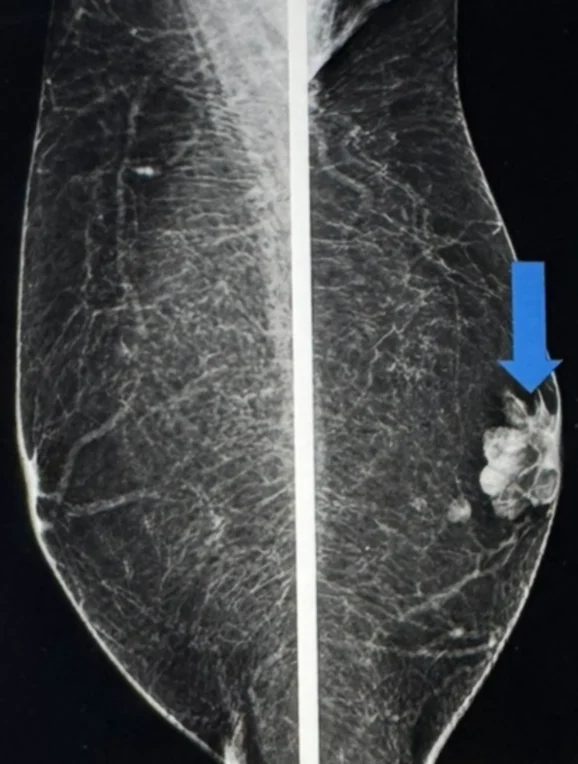

If something suspicious is found, medical imaging is used to investigate. Mammography, ultrasound, and sometimes MRI can distinguish between cancers and benign growths such as lipomas, haemangiomas, or fibroadenomas, but biopsy remains the definitive test.

There are four main types of breast cancer relevant to men. Ductal carcinoma in situ is confined to the ducts. Inflammatory breast cancer causes redness, swelling, and warmth of the breast. Invasive ductal carcinoma, which appears as a firm, painless lump, is the most common type in men. Paget’s disease of the nipple begins in the ducts beneath the nipple and presents with swelling and discolouration.